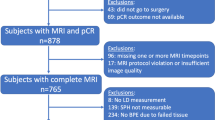

The case files of 143 patients aged 27–73 years with complete clinical data were collected from January 2018 to April 2022. There were 77 premenopausal and 66 postmenopausal women. Molecular typing revealed that 72 cases were hormone receptor-positive, 40 cases were triple-negative breast cancer, and 62 cases were HER2 positive breast cancer. The complete response rate of neoadjuvant therapy was 48.25% (69/143), defined as CR + PR/total = 92.31% (132/143) based on the objective response rate (ORR) previously studied (Table 1). A CONSORT diagram is shown in Fig. 1.